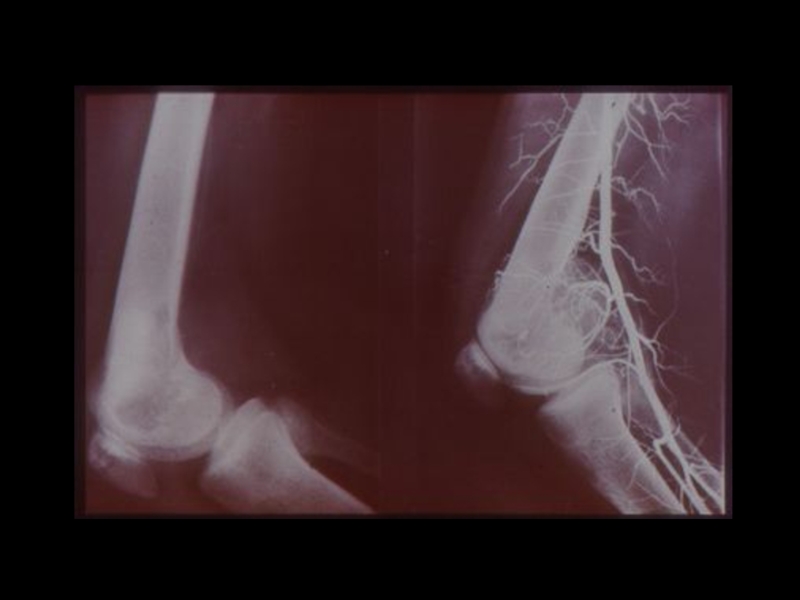

3. Специальные методы

(урография, бронхография, ангиография,

лимфография, пневмоартрография и другие)